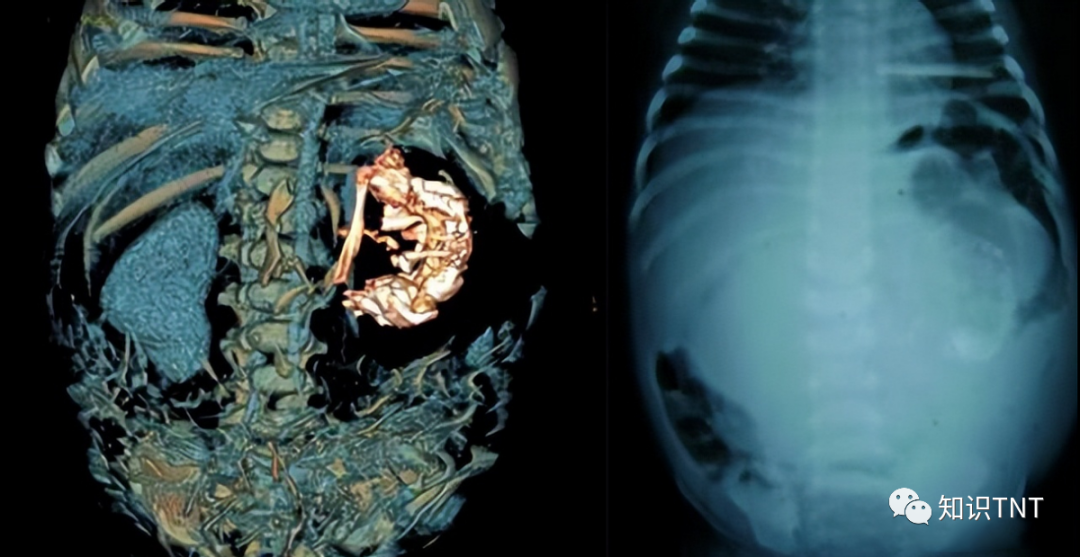

黄太老吃完饭后,喜欢出门散会步,消消食,这天却不慎摔了一跤,儿子罗先生赶到后,急忙将母亲送往医院。老人家年事已高,医生不敢马虎,给黄老太做了个全身CT检查,这一检查吓了一跳,黄老太的肚子里居然有一个成形的胎儿影像!医生震惊得不行,一般来说,女性在50-55岁之间就会因为卵巢内卵泡生理性耗竭,卵泡将不再分泌雌性激素,从而导致绝经。要知道,黄老太可是有着91岁的高龄,怎么可能会怀孕?医生怀疑是机器坏了,又给黄老太照了一次,结果还是一样的,再三考虑之后,医生还是跟罗先生说了。

“你的母亲可能怀孕了”,这句话如一道惊雷,将罗先生炸得五雷轰顶,他思来想去也想不通,自己的母亲怎么可能怀孕?就算真的有医学遗迹,年到90还不绝经,但这也不是一个人的事啊!自己的父亲50年前就去世了,黄老太难道还能背着自己跟人私会不成?想到这里,罗先生觉得脸上蒙羞,他不太愿意相信,将母亲从县医院转到市医院。市医院同样给黄老太拍了CT,图像更为清晰,可以清楚地看见黄老太的肚子里有一个完整的胎儿影像,医生说,胎儿已经失去生命迹象,也就是说,黄老太肚子里的是个死胎!医生猜测,难道黄老太身上有个寄生胎?寄生胎,顾名思义就是寄生在黄老太身上的胎儿,它的形成是因为母体怀了一对双胞胎,发育不好的胎儿会被正常发育的胎儿吸收,被吸收后,残余的肢体、器官等会寄生在正常发育的胎儿身上,也被称为“孪漏遗生症”,发病的概率很低,只有五十万分之一。被寄生的胎儿多表现为肚子明显比正常人大。这一点,黄老太倒是符合,多年来,她的肚子一直比正常人大。但是通常来说,寄生的胎儿是不完整的,只有残缺的肢体、器官,黄老太肚子里的影像却很完整,头脑、四肢都有,医生还测量了一下,胎儿有24-26公分长。就在医生百思不得其解时,黄老太终于从摔倒中恢复意识,揭开了一个尘封多年的秘密,她说,“这是我的幺儿。”

黄老太觉得胎儿对自己也没有影响,就决定将它留在肚子里,特别是老伴死后,对于黄老太来说,肚子里的胎儿就是另一种形式的陪伴。听完黄老太的话后,医生还是觉得不可思议,一个死胎怎么可能会在黄老太的子宫里待60年?一般来说,胎儿死后的腐肉会感染子宫,从而导致子宫病变,可黄老太一直没有被感染的迹象。医生又对胎儿做了一次检查,发现胎儿死体呈高度钙化,与黄老太的脊柱叠在一起,这很显然是宫外孕,受精卵在子宫体腔以外着床,发生宫外孕的几率为二万分之一,最常见着床部位为输卵管,也有少部分卵巢、宫颈、腹腔,黄老太就是极少数在腹腔着床的。

医生解释,死胎一直未腐烂,是因为胎盘包裹住了死胎,像一层保鲜膜一样,使得死胎长年没有腐烂,长年累月下来,死胎便高度钙化,好好地保存在黄老太肚子里,也不会对她的身体造成影响。知道真相后,罗先生总算松了一口气,原来自己还有个从未出世的弟弟。死胎对黄老太的身体没有影响,治好摔倒造成的伤后,罗先生就将黄老太接回家了。想想黄老太也是不容易啊,对于一般女人来说,怀胎十月就已经够受罪的了,而黄老太一怀就是60年,但对她来说,这也是老伴对自己另一种形式的陪伴吧。#打开眼界##我要上微头条##怀孕##老人#